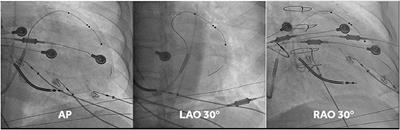

Published on 14 Jul 2022

in Cardiac Rhythmology